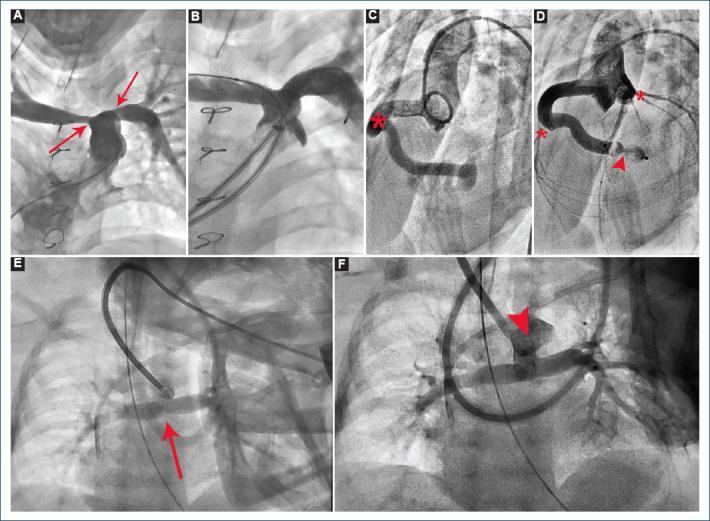

Congenital heart disease is the most common birth defect and the leading cause of childhood mortality in high-income countries. In these countries, the prognosis for a child born with congenital heart disease is excellent, with over 90% achieving adulthood. However, in the low and lower-middle-income countries, as ours, the outlook is starkly different. In Chiapas, because of the progress of the hemodynamics program, more and more types of congenital heart diseases are susceptible to being treated by cardiac catheterization.

To show the global experience of the interventionism in congenital heart diseases in Chiapas from its inception to recent days.

Through a retrospective study from April 2016 to June 2023, we reviewed the electronic files of the total of patients who underwent cardiac catheterism during the same period of time.

A total of 1000 procedures were performed, 581 in female patients, with a median age of 4 years (1 day to 77 years). Of the total procedures, 115 (11.5%) were diagnostic catheterizations and 885 (88.5%) were interventional.

Cardiac catheterization in pediatrics in Chiapas has displaced cardiac surgery in a large percentage, and the results that have been obtained are undoubtedly encouraging, which already represents a decentralization in the care of congenital heart diseases in our country.